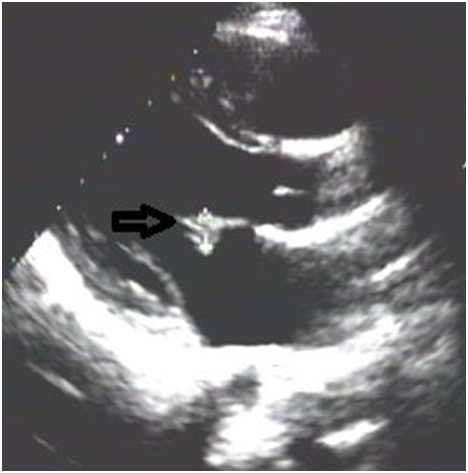

A 53 year old male vegetarian, not diabetic or hypertensive and did not have a history of cardiovascular, hepatic or kidney disease, presented to us with vague pain and worsening swelling of both lower limbs since 1 week. Physical examination was unremarkable except for bilateral tender pitting edema of feet, legs and thigh. Investigations showed Hb 116g/L,WBC count 8.9 X 109/L, platelet 301 X 109/L, ESR 72mm/hr, blood urea nitrogen 21mmol/L, serum creatinine 132 micromol/L, Urine albumin nil. Saturation was 98% in room air. Chest X ray was unremarkable. Venous doppler study of lower limbs unmasked DVT involving bilateral saphenofemoral, superficial popliteal and popliteal veins with normal arterial doppler. Tc-99m lung perfusion was normal. LFT, fasting lipid profile, electrolytes and thyroid function were normal. HIV, HBsAg and anti HCV were negative. Protein C, protein S activity, antithrombin III, factor V leiden mutation, APLA were unremarkable but a high total plasma homocysteine of 29.76umol/L(5.46-16.20umol/L). B12 level was low (188pg/ml) and he was given IM. methylcobalamin 1000mcg for 7 days. CT Venogram showed chronic thrombosis of the IVC and bilateral renal veins with acute thrombosis in bilateral common iliac, external/internal iliac, bilateral common femoral and superficial femoral veins (Figure 1).

Figure 1 CT Venogram showed hypoplastic IVC as depicted by thinned out IVC with chronic thrombosis(white arrows) with acute thrombosis in bilateral common femoral/superficial femoral veins depicted by distended veins when compared to the arteries(black arrows).